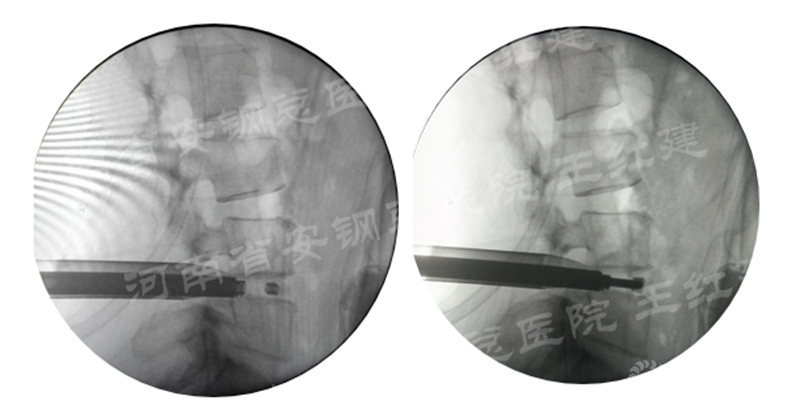

应用通道技术进行植入融合时,首先要更换工作套管,通过枪钳、抓钳的应用处理椎间盘,接着进行自体骨或同种异体骨及cage植入,并通过C臂透视确定试模型号放置融合器,最终完成植骨融合。

确定融合器位置

在固定的步骤可以先期进行经皮螺钉置入,再进行融合器的置入,进而实现充分固定。

手术步骤:先期经皮螺钉置入、再进行融合器的置入